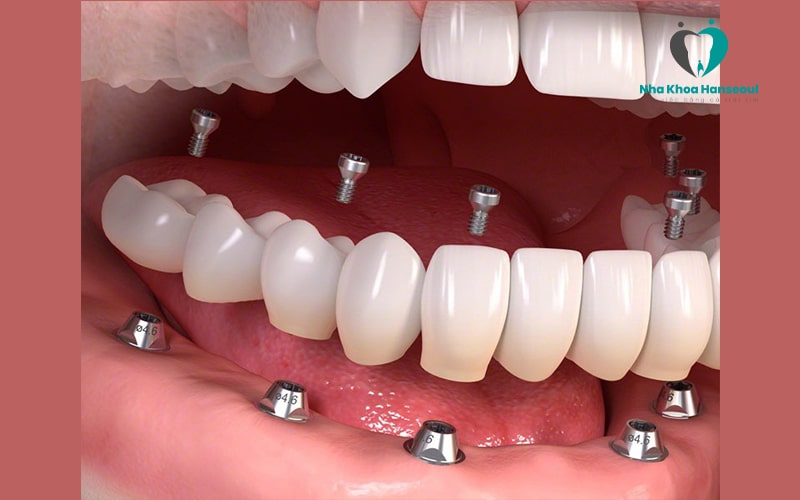

Cấy ghép Implant All On 4 là giải pháp với kỹ thuật cấy 4 trụ Implant vào xương hàm của bệnh nhân. Tuy nhiên, để sử dụng kỹ thuật này thì xương hàm của bệnh nhân phải đủ chắc chắn và đủ dày để hỗ trợ các implant được vững chắc.

Thông thường vị trí đặt trụ implant của kỹ thuật All On 4 thường là: 2 trụ đặt thẳng đứng ở nhóm răng cửa trước. 2 trụ đặt theo góc nghiêng 30 – 45 độ ở nhóm răng hàm. Tuy nhiên, vị trí đặt trụ implant không phải ai cũng giống nhau. Mỗi bệnh nhân sẽ được bác sĩ nha khoa tư vấn cụ thể, chi tiết sau khi thăm khám kỹ càng.

Sau khi cấy implant all on 4, bác sĩ sẽ sử dụng một hàm răng giả hoặc các nhịp cầu răng để phục hình lên phía trên giúp bệnh nhân thuận lợi ăn nhai.

2.4 Implant All On 6

Implant All On 6 là giải pháp cải tiến hơn all on 4 khi sử dụng 6 trụ Implant để đặt vào xương hàm bệnh nhân. Với kỹ thuật All On 6, các trụ chân răng thường được dựng thẳng đứng. Vị trí lắp đặt cũng được phân bố đều khắp cả hàm.